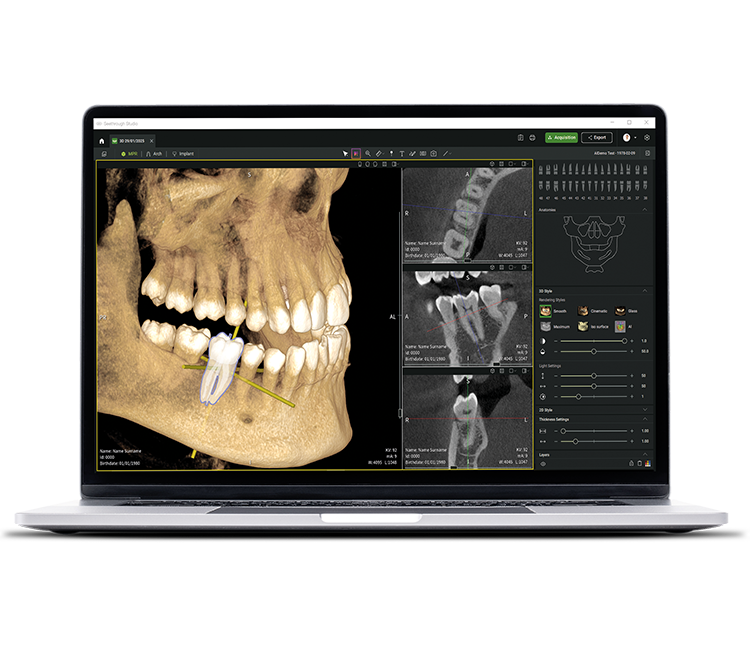

• Seethrough Studio

See tomorrow. See a new level.

Además de las sofisticadas tecnologías de hardware, el revolucionario software Seethrough Studio es el factor decisivo para el alto nivel de toda la gama de productos radiológicos de W&H. Con funciones útiles y algoritmos avanzados, Seethrough Studio es una solución completa que lleva los flujos de trabajo digitales y de radiología en odontología a un nuevo nivel.

Herramienta de planificación de implantes integrada

Además de la excelente calidad de imagen y el uso intuitivo, Seethrough Studio ofrece numerosas funciones útiles, como la herramienta de planificación de implantes integrada de serie para facilitar la visualización y la preparación del tratamiento.

Funciones asistidas por IA

Seethrough Studio utiliza varias herramientas de IA para obtener imágenes aún mejores, como la alineación de volúmenes 3D, la segmentación de dientes, la generación de líneas de arcos, el reconocimiento automático de nervios y una ayuda útil en la detección de patologías.